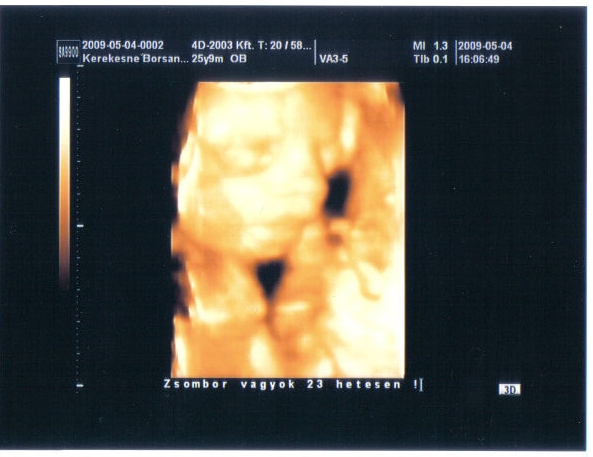

Linácska, Tündi: a babák nagyon hasonlítanak egymásra,